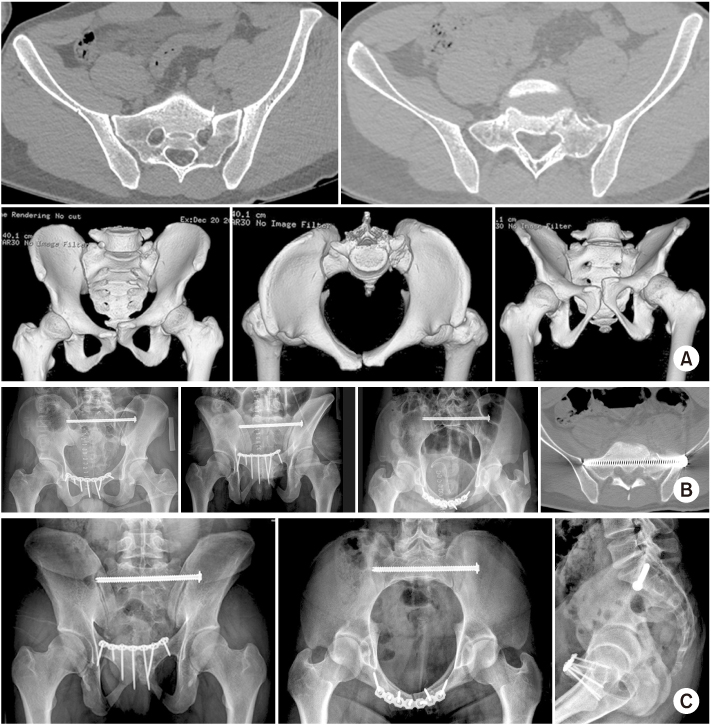

Fig. 8

(A–C) A 63-year-old male sustained an unstable pelvic injury with spino-pelvic dissociation. (B, C) The spino-pelvic fixation was performed and showed the iliac screw, which was used with the connecting rod. (D) The radiograph after 12 months showed the maintenance of pelvic ring.

Fig. 9

(A–C) S2 alar-iliac (S2AI) screw should be toward the AIIS and passed just over the superior rim of the greater sciatic notch, above the greater sciatic notch. (D) The screw trajectory was from the dorsal cortex of the sacrum to the inner ilium by penetrating the sacro-iliac joint.

Fig. 10

(A) A 57-year-old male sustained an unstable pelvic injury with L5 body fracture. (B) First, the pedicle screw of L4 and L5 was placed percutaneously and made the entry portal for the S2 alar-iliac (S2AI) screw. (C) The postoperative radiographs showed the functional reduction of the pelvis. (D) Follow-up radiographs at eight weeks showed the maintenance of reduction adequacy.